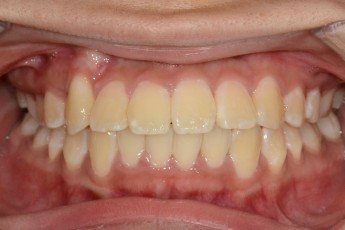

BEFORE & AFTER